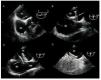

Contrast TEE and color Doppler should be considered if the transthoracic study is negative or dubious but strong clinical suspicion of PFO remains. Transesophageal echocardiography permits detailed study of the interatrial septum as it visualizes the lack of septum primum coaptation over the fossa ovale (Figure 3). Schuchlenz et al32 showed that PFO size, measured by balloon inflation during the closure procedure, correlates well with the septum primum-septum secundum distance measured by TEE.

Figura 3. Transesophageal echocardiography during percutaneous patent foramen ovale (PFO) closure procedure using an Amplatzer device (AGA Medical Corporation, Plymouth, Minnesota, USA). A: the existence of PFO (arrow) is demonstrated. B: passage of the guide through the PFO with deployment of the disc (arrow), which will be implanted in the left atrium. C: deployment of the second disc (arrow) in the right atrium. D: contrast study showing absence of residual shunting. RA indicates right atrium; LA, left atrium; Ao, aortic valve; SVC, superior vena cava.

Before interventions, TEE facilitates ruling out other possible causes of cardiac emboli, locating and checking the number of defects, and determining whether other concomitant lesions exist. During the intervention, TEE provides direct monitoring guidance in deploying the device to ensure it is correctly positioned and avoid complications or interference with other structures. It also facilitates measuring tunnel size and characterizing tunnel shape. These data are important because in very long or very tortuous tunnels some authors argue against crossing the PFO and suggest using transeptal puncture as an alternative means of achieving adequate device deployment.33 Finally, during the intervention, TEE is extremely useful to determine the size of the device to be implanted (Figure 3).